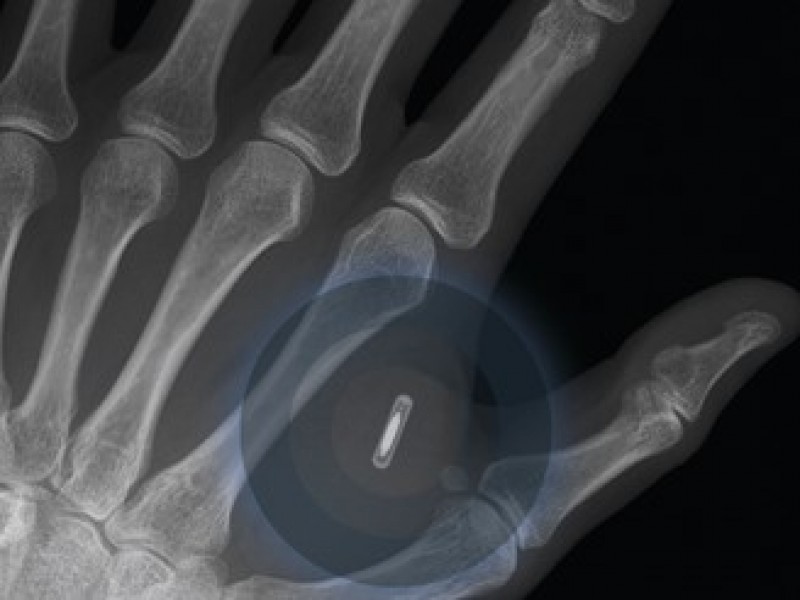

Microagulhas permitem depositar pontos quânticos sob a pele (Foto: Divulgação Kevin J McHugh MIT)

Na experiência, publicada na quarta-feira (18/12) no Science Translational Medicine, a equipe do MIT uso adesivos com microagulhas para depositar os pontos sob a pele de cobaias e depois conseguiu reconhecer a mensagem com uso de um smartphone, alterado para detectar luz quase infravermelha, invisível a olho nu. Os testes foram feitos também com corpos humanos de vários tons de pele. A mensagem persistiu por nove meses. Os cientistas acreditam que, no estágio atual da pesquisa, a mensagem se mantenha estável por cinco anos.

Pesquisadores liderados por uma equipe do Instituto de Tecnologia de Massachusetts (MIT) criaram uma plataforma de microagulhas usando micropartículas fluorescentes chamadas pontos quânticos (QD), que podem fornecer vacinas e, ao mesmo tempo, codificar invisivelmente o histórico de vacinas diretamente na pele. Os pontos quânticos são compostos de nanocristais, que emitem luz infravermelha próxima (NIR) que pode ser detectada por um smartphone especialmente equipado. Testes usando a plataforma mostraram que QDs entregues a amostras de pele humana ainda eram detectáveis após fotodegradação que simulavam cinco anos de exposição à luz solar e permaneceram detectáveis por até nove meses quando testados em ratos.

As microagulhas usadas no estudo relatado são feitas a partir de uma mistura de açúcar dissolvível e um polímero chamado PVA, além do corante de pontos quânticos e, se apropriado, da vacina. Quando o adesivo é aplicado na pele, as microagulhas, com 1,5 mm de comprimento, se dissolvem parcialmente, liberando sua carga útil em cerca de dois minutos.

Ao carregar seletivamente micropartículas nas microagulhas, os adesivos proporcionam um padrão na pele invisível a olho nu, mas podem ser digitalizados com um smartphone que remove o filtro infravermelho. O adesivo pode ser personalizado para imprimir diferentes padrões que correspondem ao tipo de vacina entregue. Testes usando pele de cadáver humano mostraram que os padrões de pontos quânticos poderiam ser detectados pelas câmeras dos smartphones após cinco anos de exposição solar simulada. Os pesquisadores também testaram a estratégia de vacinação em ratos, usando adesivos de microagulhas que liberavam os pontos quânticos junto com uma vacina contra a poliomielite. Eles descobriram que esses ratos geraram uma resposta imune semelhante à resposta de ratos que receberam uma vacina tradicional contra a poliomielite injetada.